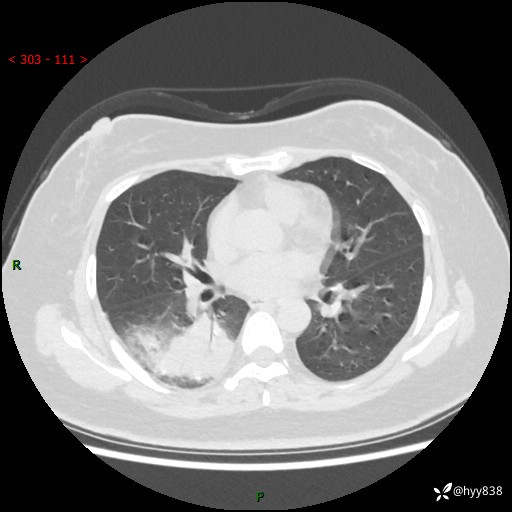

大叶性肺炎的表现形式,晒晒鉴别诊断吧…结果公布~

简要病史:患者8天前无明显诱因出现咳嗽、咳痰,为绿色脓痰,无明显加重与缓解因素,无高热、寒战,无呼吸困难,无大量脓痰,无哮鸣音,于当地医院行胸片示右下肺团块影,性质待定,予口服药物治疗症状未见明显改善,具体药名不详,为求进一步诊治来我院就诊,门诊以“肺占位性病变”收入我科进一步诊治。 患者自发病以来,精神、饮食尚可,睡眠欠佳,大小便正常,体力、体重未见明显异常。

辅助检查:CT

胸部CT平扫